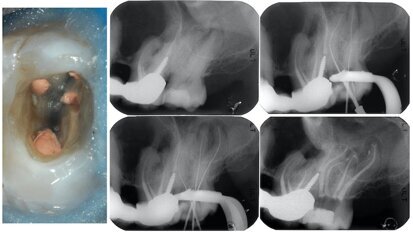

Endodontic follow-up in strongly curved root canals

The lasting success of any root canal therapy is always only apparent after long-term observation. In this article, based on a case study, the author ...